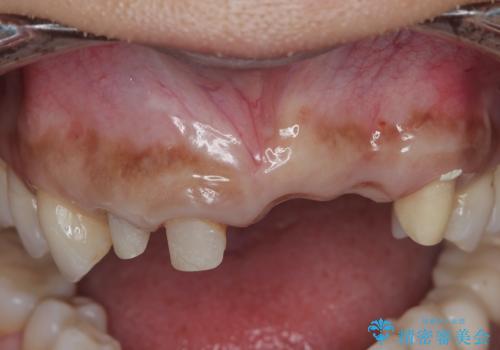

抜歯時に可及的に歯肉のボリュームを保つよう骨充填材とコラーゲン製剤による填塞を行い審美的かつ機能的なブリッジとなるよう治療を進めます。

- 66万円(ジルコニアクラウン×5・仮歯×5)費用は治療当時の料金となります